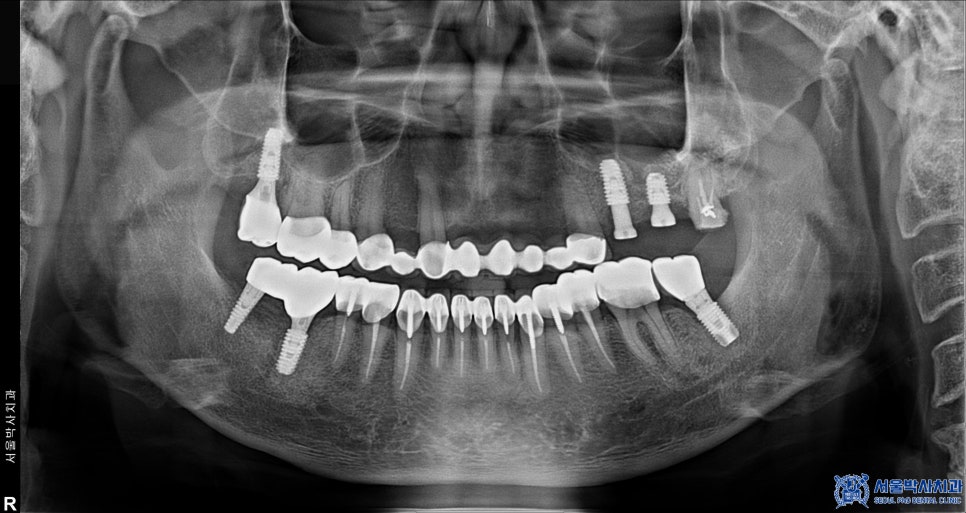

위 환자분께서는 예전에 다른 치과에서

아래쪽 어금니에 임플란트를 하셨었는데,

사용하시던 임플란트가 파절되면서

제대로 기능하지 못해 불편함을 느끼시곤

신흥동치과 서울박사에 내원해 주셨는데요.

오른쪽 아래 기존 임플란트 중 뒤쪽 큰 어금니는

임플란트와 인공 치아를 연결해주는 부분이 파절되었고

앞쪽 큰 어금니 임플란트는 염증으로 인해

상태가 좋지 않았기 때문에

제거 후 재수술을 진행해야 했습니다.